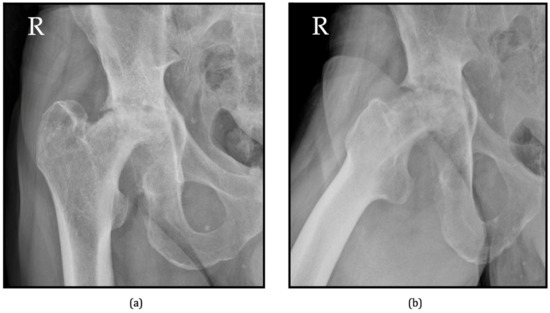

6.1. Radiographs

- Flemming, D.J.; Gustas-French, C.N. Rapidly progressive osteoarthritis: A review of the clinical and radiologic presentation. Curr. Rheumatol. Rep. 2017, 19, 42. [Google Scholar] [CrossRef]

- Rosenberg, Z.S.; Shankman, S.; Steiner, G.C.; Kastenbaum, D.K.; Norman, A.; Lazansky, M.G. Rapid destructive osteoarthritis: Clinical, radiographic, and pathologic features. Radiology 1992, 182, 213–216. [Google Scholar] [CrossRef]

- Chau, H.T.H.; Wong, P.Y.; Pan, N.Y.; Ma, K.F.J. Rapidly destructive hip osteoarthritis: A diagnosis not to miss. Br. J. Radiol. 2024, 97, 1526–1533. [Google Scholar] [CrossRef]